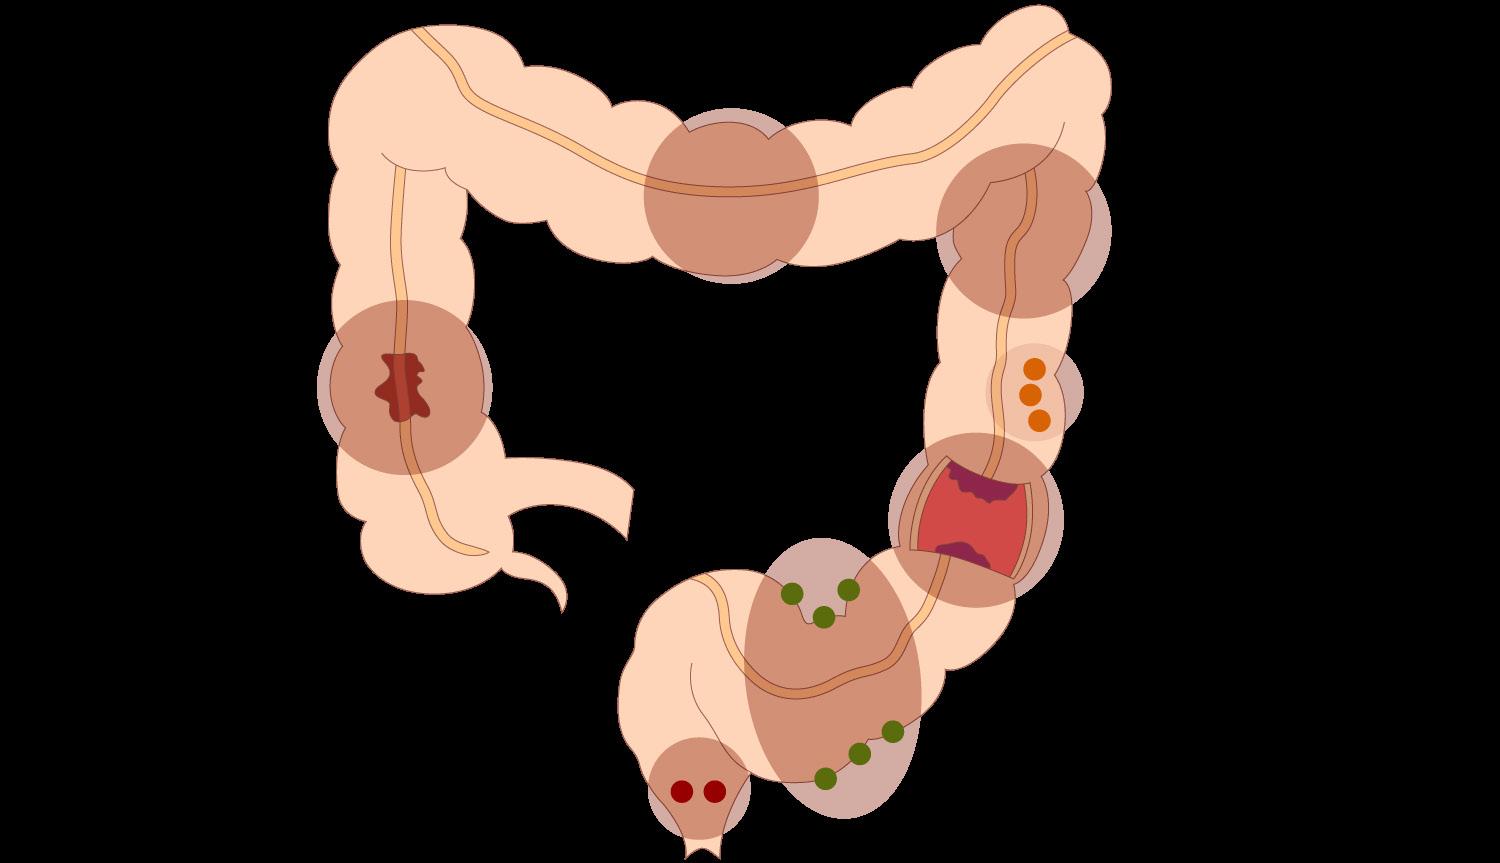

Endocarditis aguda causa más frecuente estafilococo aureus (estafilococo dorado) suele afectar a las válvulas sanas por lo general, fatal en 6 semanas si no se trata

Endocarditis subaguda causa más frecuente estreptococos del grupo viridans válvulas nativas dañadas previamente causa común de después de procedimientos dentales

En casos de estreptococo bovis se asocia con cáncer o pólipo en el colon.

Enterococos (especialmente, Enterococcus faecalis) causa común después de ITU nosocomiales

Endocarditis micótica causa más frecuente Cándida parapsilosis pacientes inmunodeprimidos (VIH o trasplante de órganos)

Válvula protésica (marcapasos o DAI):

Precoz: < 1 año tras la cirugía la etiología más frecuente es el estafilococo epidermidis (coagulasa negativo)

Tardía: > 1 año tras la cirugía destaca estafilococo aureus (coagulasa positivo)

ADVP (Adictos a droga por vía parenteral):

El germen más frecuente es S. aureus la válvula más afectada es la tricúspide

Las vávulas más afectadas son las izquierdas, aórtica seguida de la mitral y la válvula tricúspide es la válvula más comúnmente afectada en usuarios de drogas intravenosas (asociada S. aureus) (ENARM 2009)

El flujo turbulento daña el endotelio de las válvulas activando la hemostasia y se forman vegetaciones asépticas formadas por plaquetas y fibrina (trombo estéril). Luego, estas se contaminan debido a una bacteriemia por un foco séptico, formándose una verruga bacteriana (vegetación séptica), la cual puede destruir la válvula (rotura de cuerdas tendinosas, músculo papilar) y formar abscesos, produciendo la clínica cardiaca; los émbolos sépticos que pasan a la circulación sistémica dan lugar a la clínica extracardiaca (en casos de ADVP, predominan los émbolos pulmonares).